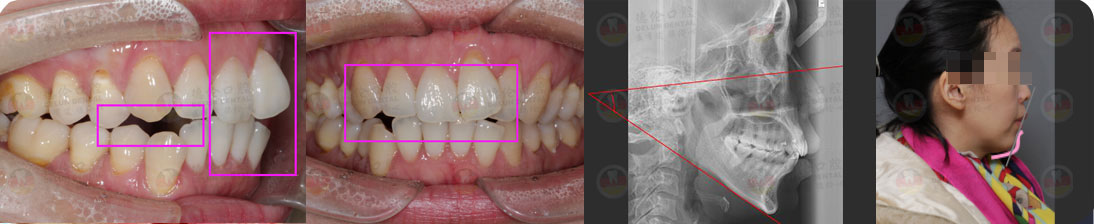

矯治前后對比

蛻變周期:上頜16個月,矯治效率提升30%,下頜12個月,矯治效率提升20%